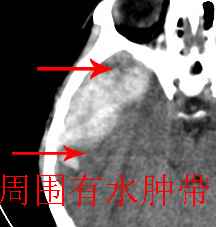

脑内及脑外并存。即:脑挫裂伤并硬膜下血肿。原因:1 后方条片状高密度影周围见水肿带。2 同侧上方 硬膜下间隙增宽。

蛛网膜下腔出血、脑内出血。(脑内高密度影密度不均、分布不均,周围有低密度水肿,无脑白质挤压征)。

依据:1.右侧颞叶不规则形血肿密度影,周围有水肿;

2.有明显占位效应;

3.颅板下硬膜下间隙存在。

脑内脑外全有,上方比较局限近似梭形改变,考虑硬膜外血肿。没有跨过颅缝,且是脑膜中动脉所在的位置。中线移位,占位效应明显。后方条带状增高影,周围有水肿带,考虑脑内血肿。